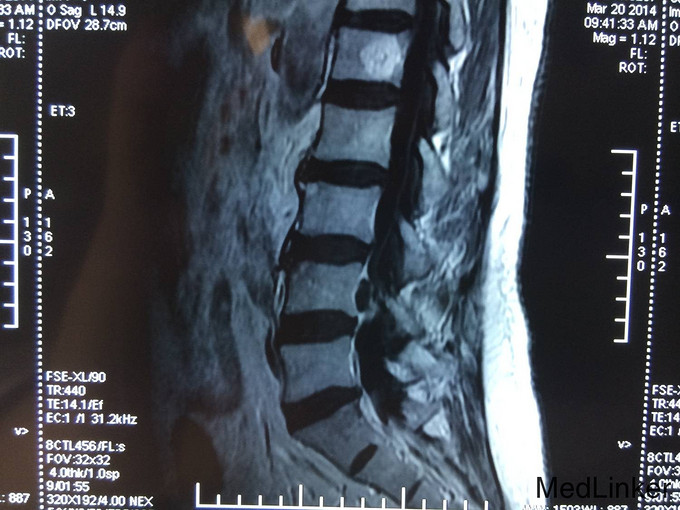

主诉:腰痛加重及左下肢疼痛1个月 现病史:患者自述腰痛10余年,休息及卧床缓解,不影响生活,未进行诊治。近一个月病情逐渐加重,腰部疼痛加重,出现左下肢麻木疼痛严重影响患者生活质量。今为求进一步治疗而来我院,我科以“腰椎间盘脱出症”为诊断收住院治疗。病来无发热,无头痛及头晕,无恶心,呕吐,无胸痛及呼吸困难,无腹胀及腹痛,饮食,睡眠较差,大小便未及异常。

专科查体:患者跛行入病房,腰椎正常生理曲线减小,腰部无明显压痛及叩击痛,髂腰肌肌力(L5,R5),股四头肌肌力(L5,R5),足趾背伸肌力(L5,R5),跖屈肌力(L5,R5),肌张力未及明显异常。直腿抬高试验(L,50°),加强试验阴性,健腿抬高试验阴性,PSR(L++,R++),ASR(L++,R++),Babinski'sign(L-,R-),双侧足背动脉搏动正常。

诊断 : 腰椎间盘脱出症,髓核游离 入院后完善检查,查无手术禁忌症后行腰椎后路椎板减压间盘切除椎间融合器椎弓根钉内固定术,术后患者左下肢疼痛缓解,术后支具保护下三天后拔除引流管后下地行走。